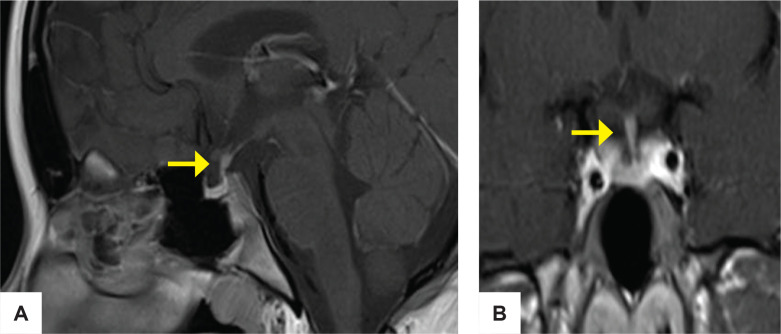

处理一个同时有垂体高分泌和低分泌表现的病人可能是令人困惑的。我们报告一个14岁的女性谁提出体重增加,多尿和烦渴。生化结果与库欣病合并中枢性尿崩症一致。垂体磁共振成像显示右侧腺瘤伴茎部增厚。两种腺瘤的免疫组化染色均为促肾上腺皮质激素、促甲状腺激素、生长激素和促黄体生成素阳性。术后,患者出现垂体功能减退并持续性尿崩症。双腺瘤的共存会给诊断和治疗带来挑战,也是手术失败的常见原因。术中评估是识别双重或多重垂体腺瘤的重要患者呈现多种分泌表现。

Managing a patient with both pituitary hypersecretory and hyposecretory manifestations may be perplexing. We report a 14-year-old female who presented with weight gain, polyuria and polydipsia. Biochemical results were consistent with Cushing disease with central diabetes insipidus. Pituitary magnetic resonance imaging showed a right adenoma with stalk thickening. The immunohistochemistry staining of both adenomas was positive for adrenocorticotropic hormone, thyroid stimulating hormone, growth hormone and luteinizing hormone. Postoperatively, the patient developed panhypopituitarism with persistent diabetes insipidus. The coexistence of double adenomas can pose diagnostic and management challenges and is a common cause of surgical failure. Intraoperative evaluation is important in the identification of double or multiple pituitary adenomas in a patient presenting with multiple secretory manifestations.